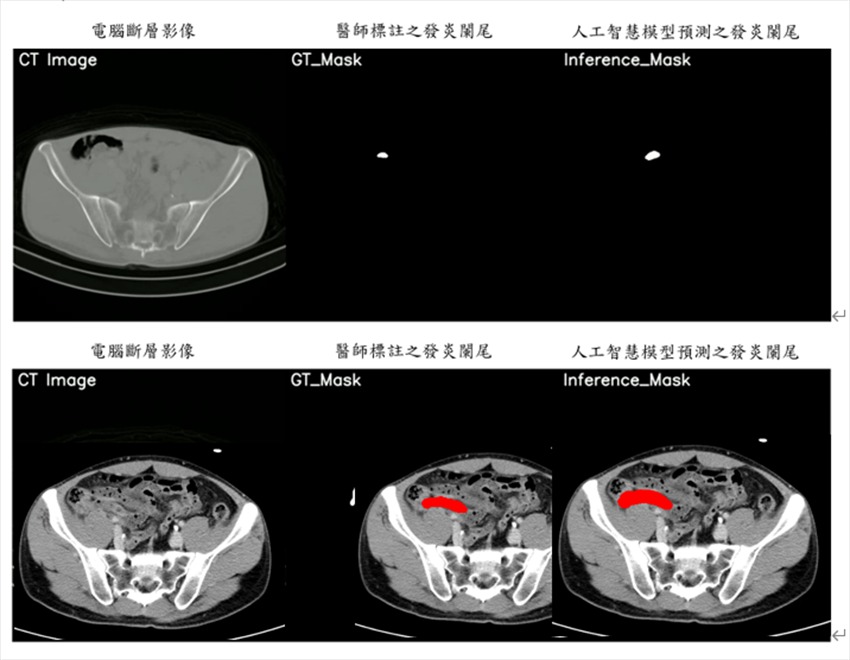

急性闌尾炎是急性腹症中最常見的原因之一,其症狀經常與其他腹部疾病相似,使得診斷充滿挑戰。即便具備臨床檢查與實驗室數據,確診過程仍然困難且耗時。元智大學與亞東醫院聯合開發的系統,運用先進的二維及三維影像分割技術,不僅能準確分辨影像中的發炎區域,還能有效提供醫療人員診斷關鍵的影像切片,大幅縮短診斷時間,降低誤診風險,改善患者的治療成果。

此次開發的系統運用深度學習技術,針對電腦斷層掃描影像進行分析與判別,能迅速判定急性闌尾炎是否為急性腹痛的根本原因。陳敦裕強調,團隊結合學術研究與實際應用,設計出符合臨床需求的解決方案,幫助醫療專業人員在時間緊迫的情況下快速做出準確判斷。

元智電機系攜手亞東影像醫學科團隊,使用電腦斷層掃描影像,進行判別是否發生急性闌尾...

元智電機系攜手亞東影像醫學科團隊,使用電腦斷層掃描影像,進行判別是否發生急性闌尾炎。 元智大學/提供